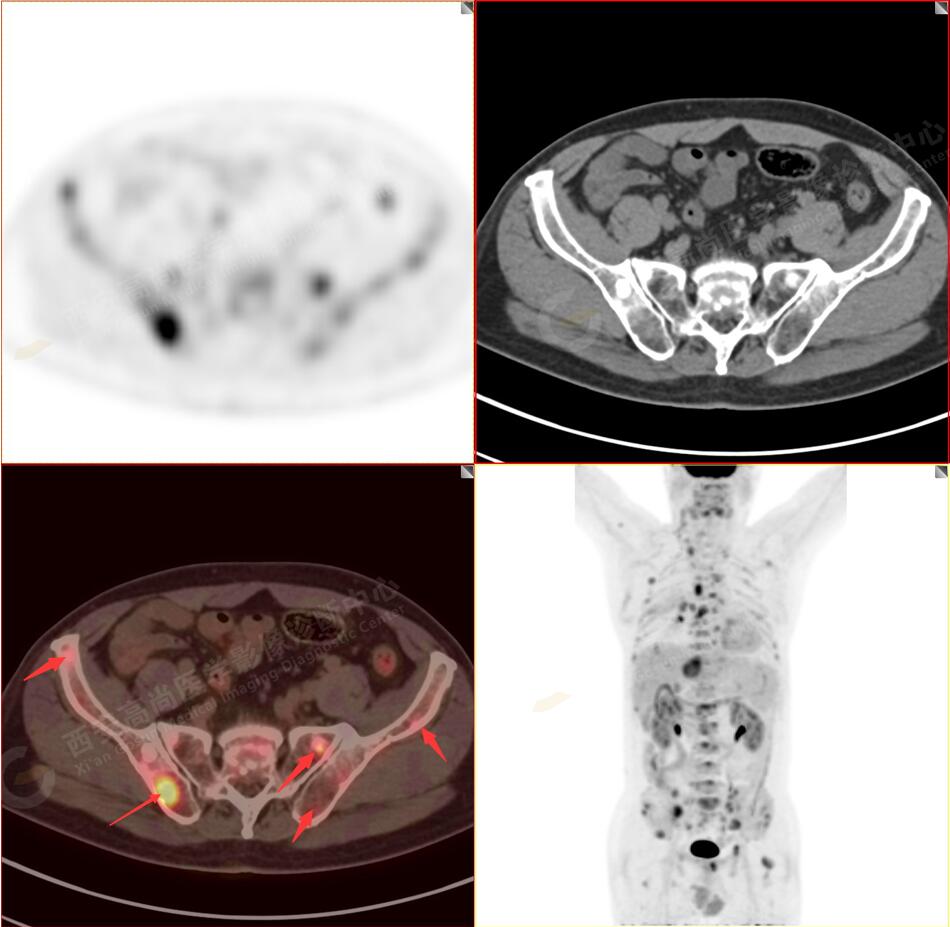

1.以下為肺內(nèi)原發(fā)灶

2.以下為全身多發(fā)轉移灶

5.右側肱骨上段、左側肩胛骨、右側鎖骨胸骨端、胸骨、雙側多發(fā)肋骨、脊柱多發(fā)椎體及附件、雙側髂骨、雙側髖臼、雙側恥骨、雙側肱骨上段多發(fā)成骨性病變,呈不同程度FDG代謝異常增高,考慮為多發(fā)骨轉移瘤。